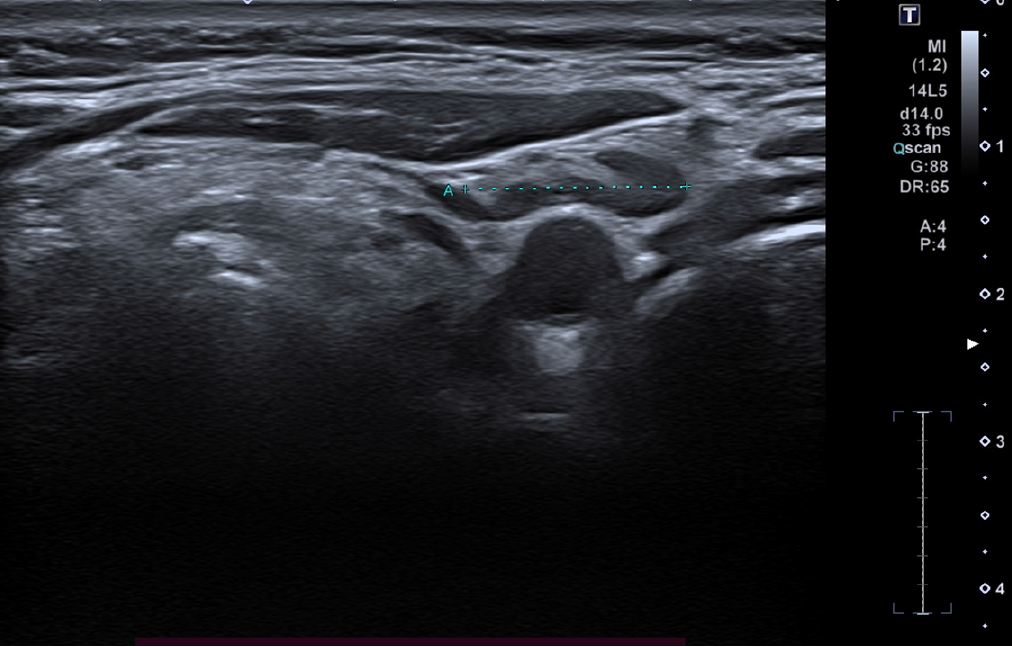

Figure 2 High-frequency ultrasound (24 MHz) image of the left laterocervical region showing a single lymph node (outlined in blue dashed line), not suspicious for metastatic involvement.

The node presents with preserved morphology, including a visible fatty hilum and a well-defined cortex, with no signs of pathological enlargement or altered echogenicity.